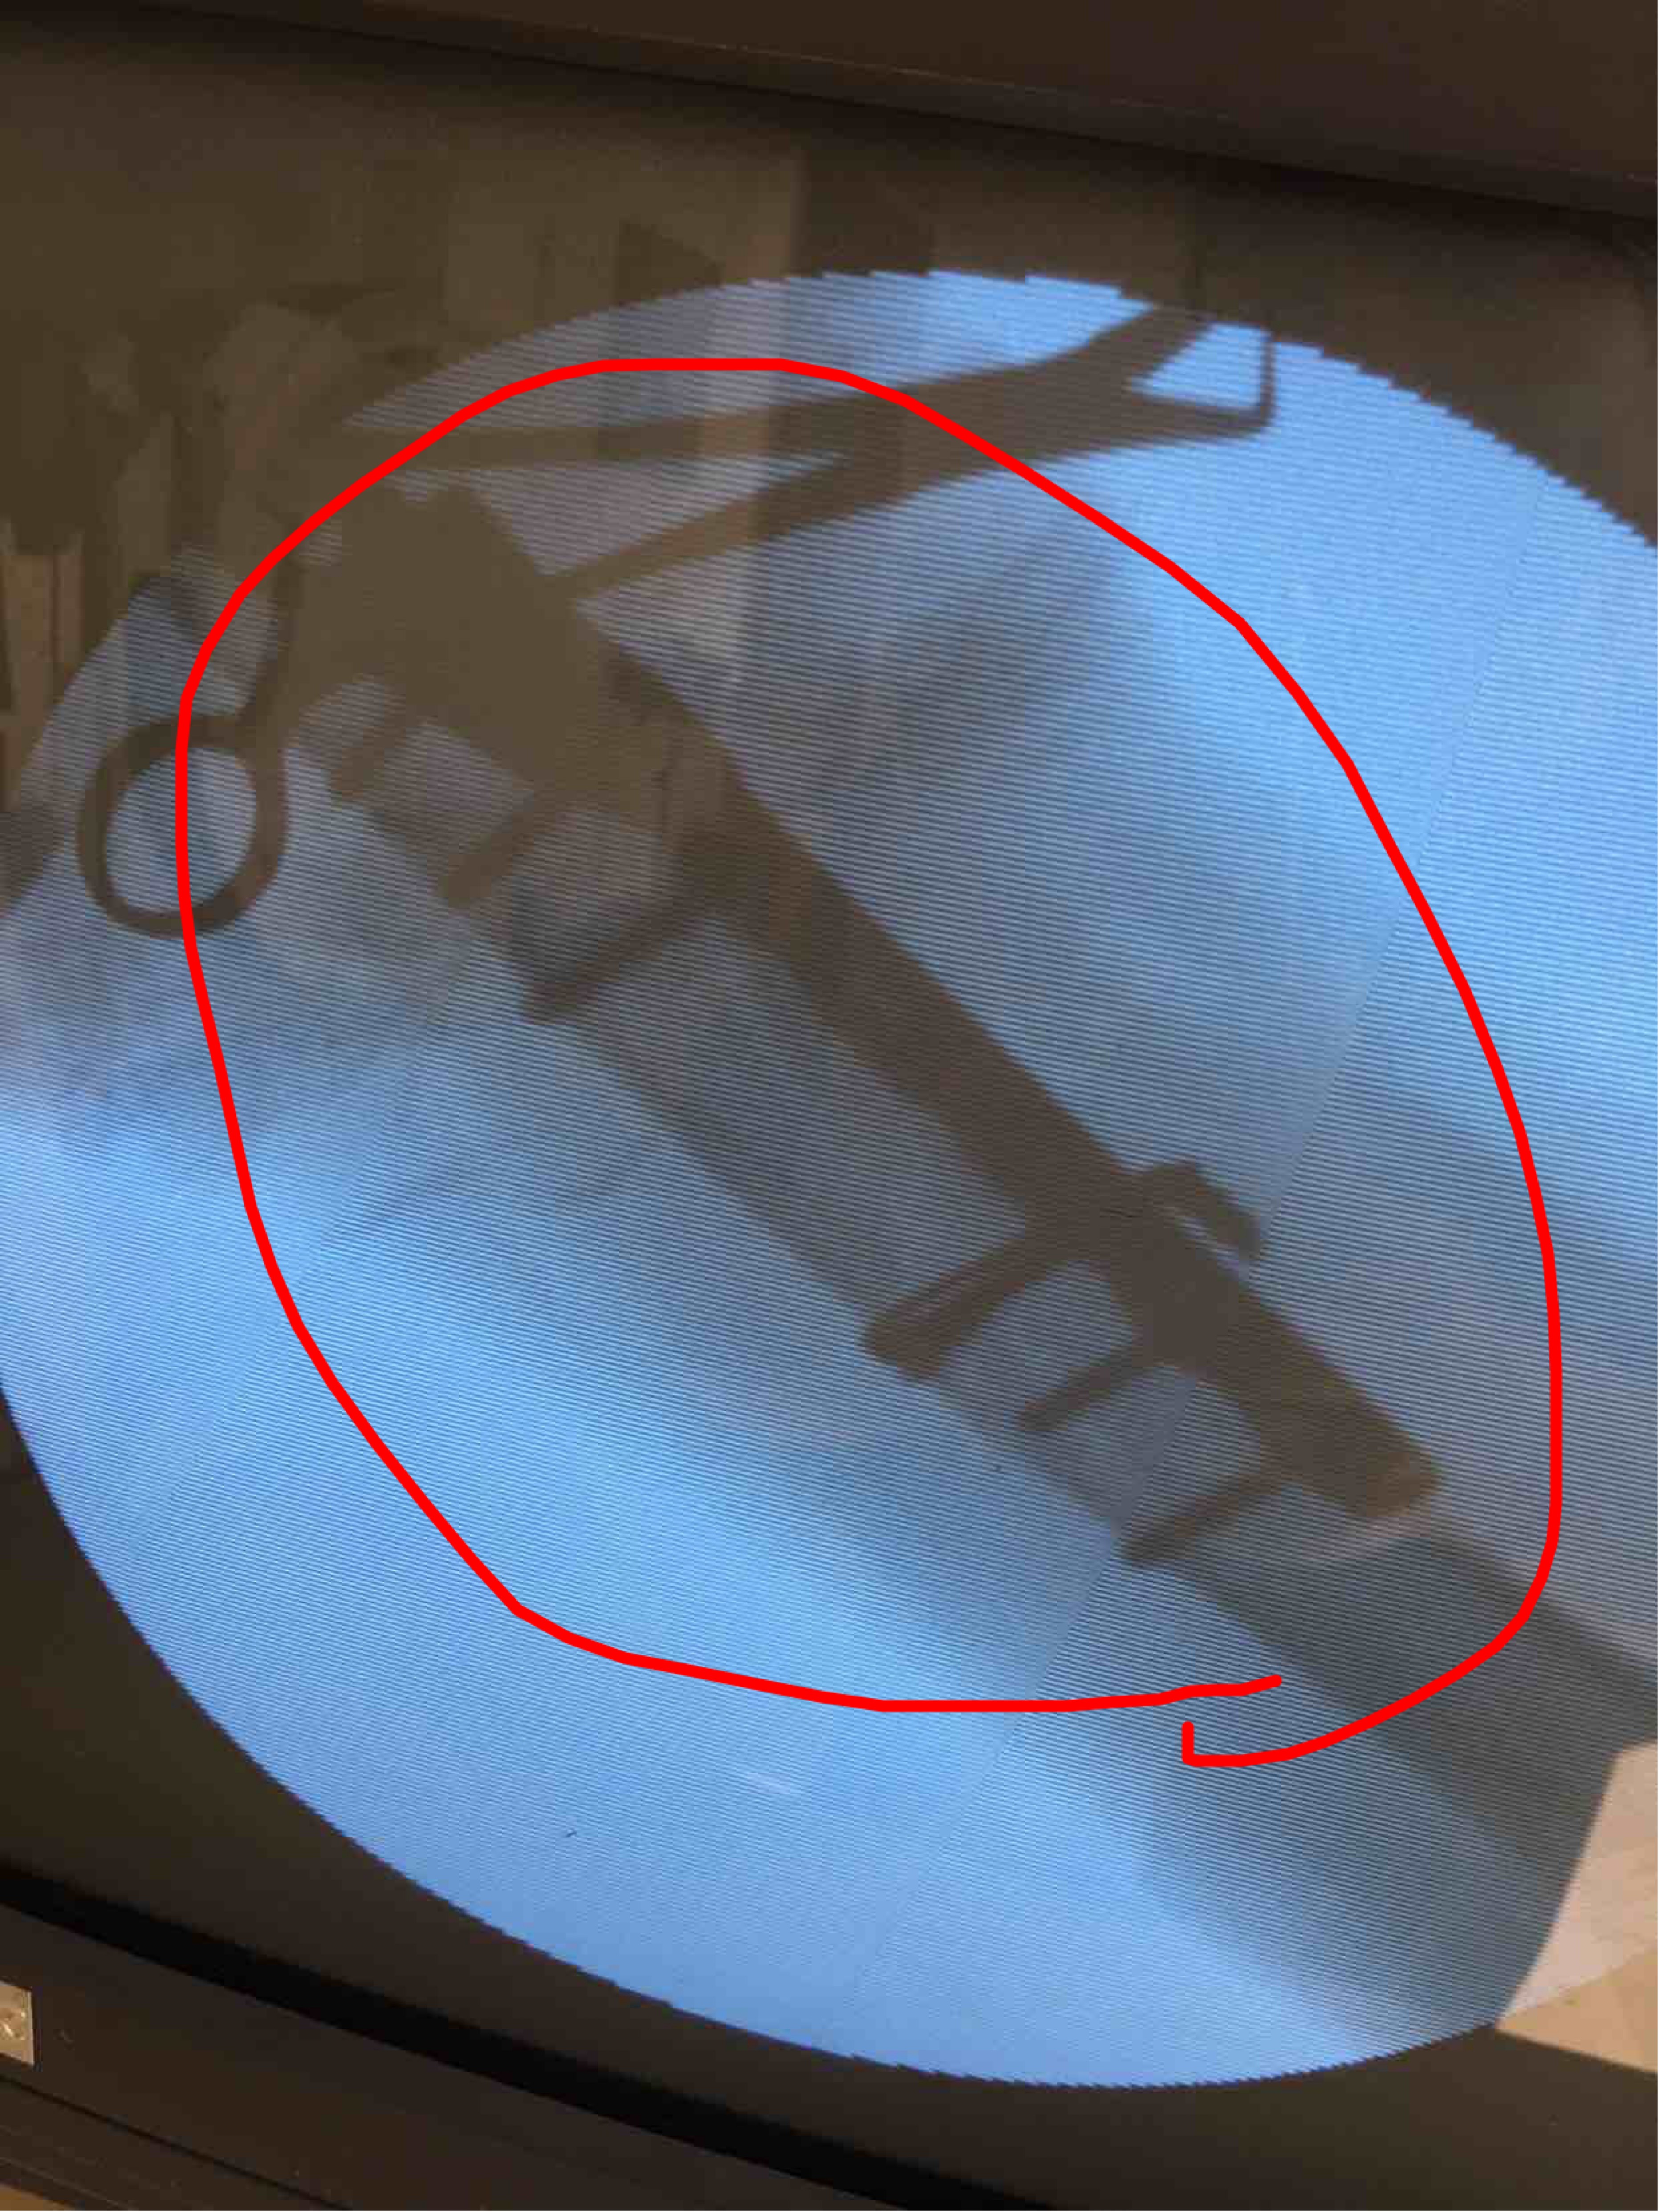

肱骨外科颈粉碎性骨折并肱骨干骨折(切复内固定术)

诊断:1.肱骨外科颈粉碎性骨折        2.肱骨干骨折完善术前准备,在臂丛麻醉下行切复内固定术,近端选择解剖型锁定钛板,干部选择普通加压钛板,术中注意充分止血,保护尺神经,固定顺序先外科颈后干部。

术中外科颈粉碎成四部分骨折,只做了立线及颈干交的复位,保证功能复位。还有不足之处望各位老师指正!谢谢!